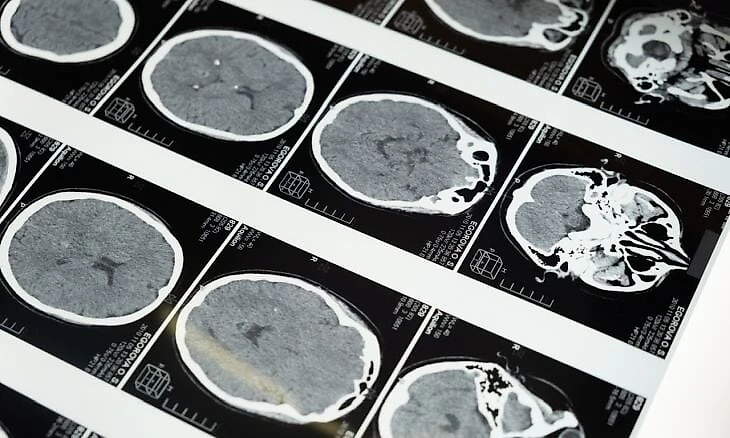

FDA уже успело провести выборочное исследование на 284 игроках школьной футбольной команды. В течение сезона 139 спортсменов носили Q-Collar, а 145 игроков – нет. Все участники также носили акселерометр, который измерял силу удара по голове во время игры. До и после окончания сезона каждый спортсмен прошел магнитно-резонансную томографию, чтобы оценить структурные изменения в головном мозге.

Существенные изменения были обнаружены в глубоких тканях мозга, участвующих в передаче электрических нервных сигналов, у 106 из 145 (73%) участников в группе без ошейника, в то время как в группе, носившей Q-Collar, значительных изменений в этих областях не обнаружено. Эти различия, вероятно, указывают на защиту мозга, обеспеченную новым устройством. В процессе исследования не было выявлено никаких побочных эффектов.